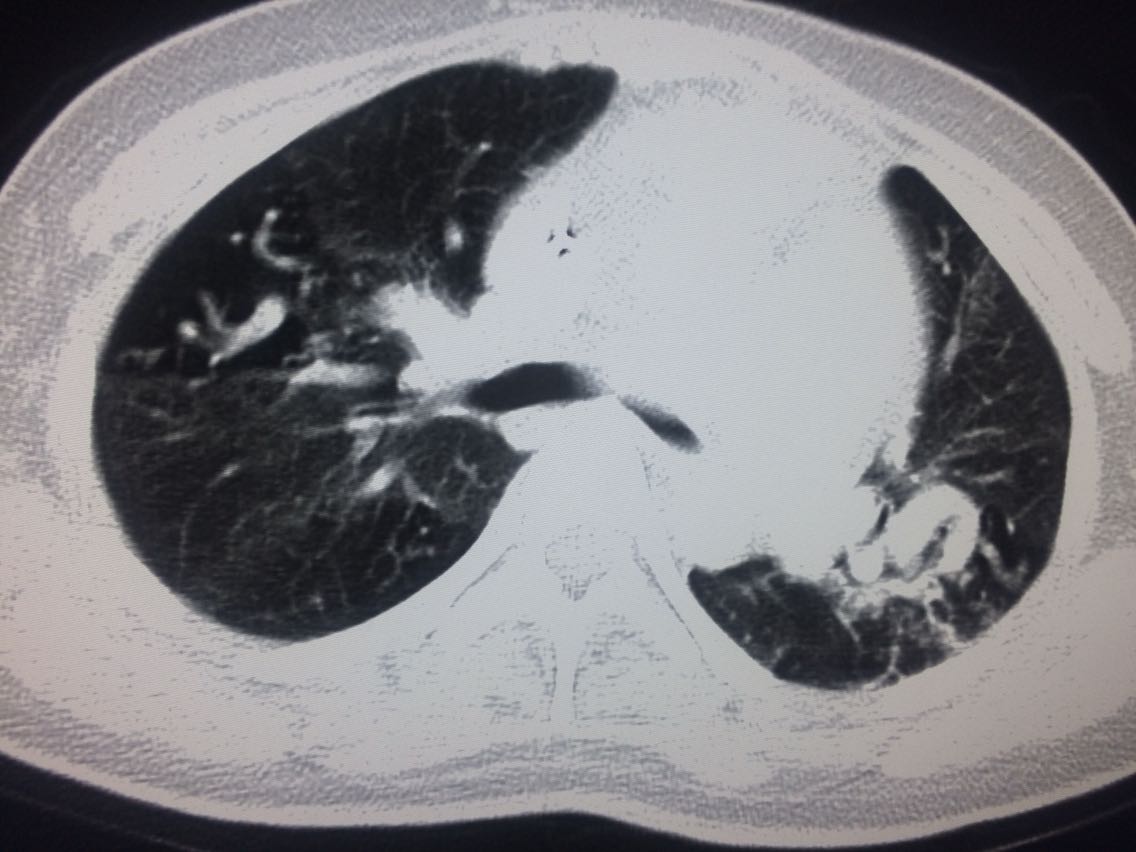

诊断,肺动脉高压。 鉴别诊断,肺动脉栓塞。 影像诊断,肺动脉高压,肺门区出现残根征,肺动脉扩张,肺动脉段膨隆,心影增大。CTA见迂曲增宽的肺动脉。 肺栓塞,影像可见典型充型缺损影,伴随肺纹理的减少。 治疗以对症处理为主,病人病史14年。 讨论诊断和鉴别诊断? 随访,症状好转。